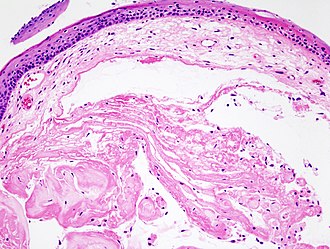

Laryngeal nodule

LM early: edema, fibroblasts proliferation; late: subepithelial hyaline / stromal hyaline, blood vessels - dilated

Features:[3]

• Early:

1. Edema.

2. Fibroblasts proliferation.

• Late:

1. Subepithelial hyaline / stromal hyaline.

2. Blood vessels - dilated.

Notes:

• No inflammation.